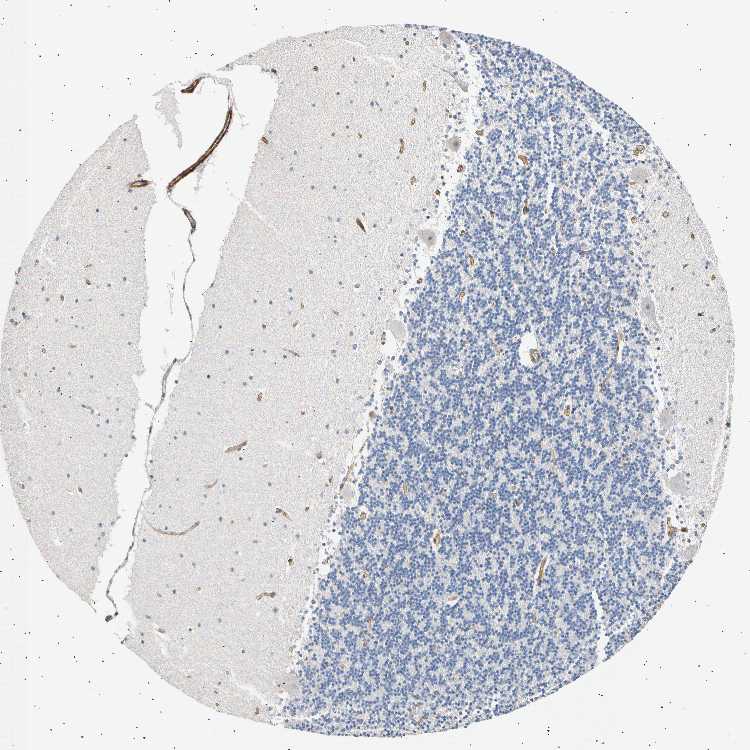

CEREBELLUM - Antibody stainingi

Antibody staining in the annotated cell types in the current human tissue is reported as not detected, low, medium, or high, based on conventional immunohistochemistry profiling in selected tissues. This score is based on the combination of the staining intensity and fraction of stained cells.

Each image is clickable and will lead to virtual microscopy that enables deeper exploration of all samples and also displays staining intensity scores, fraction scores and subcellular localization as well as patient and tissue information for each sample.

Antibody HPA008025

Purkinje cells Not detected

Cells in granular layer Not detected

Cells in molecular layer Not detected